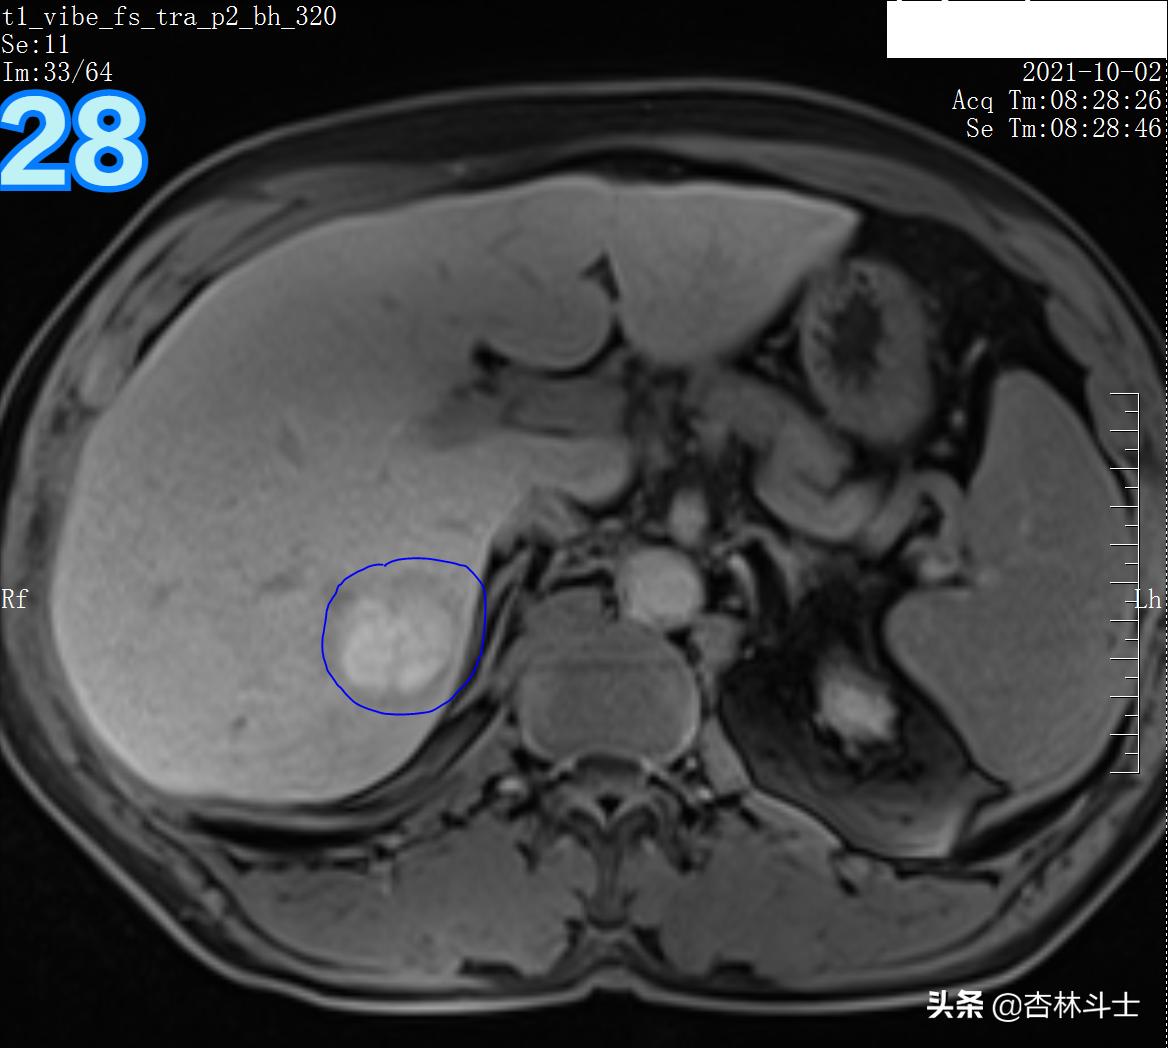

T1压脂肝胆特异期

总结:10月份复查,肝右后叶下段新发一个直径约1㎝的结节,T1呈等信号,T2呈稍高信号,弥散加权序列可见弥散明显受限,增强动脉期明显均匀强化,门静脉期出现对比剂廓清,呈略低信号,平衡期信号进一步减低,肝胆特异期未见特异性对比剂摄取呈低信号。增强特征为典型的“快进快出”,影像学上典型的肝细胞癌表现。